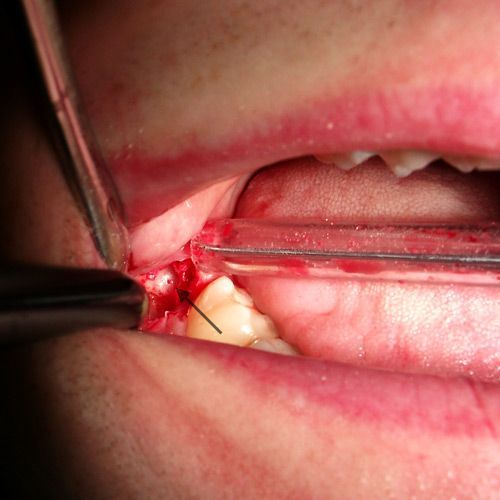

Auch bei gründlicher Inspektion des Leerkieferabschnittes im Bereich des 4. Quadranten konnte optisch kein Herd oder Störfeld ausgemacht werden. Es wurde trotzdem ein OP-Termin vereinbart, weil der Patient angab, dass er immer, wenn er über die entsprechende Zahnzone des 48. behandelt wurde, tagelang keine nennenswerten Schmerzen und Bewegungseinschränkungen mehr hatte. Dieser Test der Störfeldbeeinflussung über die entsprechenden Reflexzonen ist viermal gemacht worden, mit immer den gleichen positiven Ergebnissen. Das war der Grund, warum der Patient sich schließlich zu einer Operation entschloss.